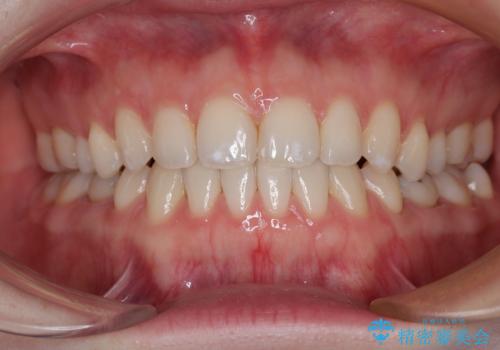

すきっ歯をインビザラインできれいな歯並びに改善

隙間や叢生の程度はそれほど著しいものではなかったので、インビザラインでもワイヤー矯正でも対応可能でしたが、極力目立たない装置を希望されたため、インビザラインにて矯正治療を行うこととしました。

すきっ歯の原因は色々ありますが、嚥下や発音時の舌突出癖が大きな原因となることがあります。

こちらの患者様も強い突出癖があったため、舌のトレーニング指導を行いました。